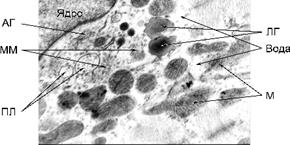

При вивченні ультратонких зрізів тканини міокарда були виявлені наступні зміни (див. рис. 1).

Мітохондрії кардіоміоцитів з дещо підвищеною електронною щільністю, дезорганізовані, а саме, розпушені кристи внутрішньої мембрани. Частина мітохондрій містить значні ділянки електронно-світлих гомогенних мас. Саркоплазма має знижену електронну щільність внаслідок підвищеного вмісту рідини. Кількість рибосом та полісом знижена, у значній кількості наявні краплі ліпопротеїдів низької щільності. У саркомерах міофібрил Z-смуги не чіткі, а також порушена структурна орієнтація волокон актину та міозину. Сарколема, переважно, згладжена, а в окремих ділянках її електронна щільність підвищена. Каріотека ядер кардіоміоцитів на більшості ділянок дезорганізована, особливо тих, що прилягають до гіпертрофованого апарату Гольджі. Останній містить збільшену кількість розширених цистерн, мікроміхурців, первинних лізосом, мультивезикулярних тілець.

Рис. 1. Будова кардіоміоцита у морських свинок за умов гострої сироваткової хвороби (набряк мітохондрій та саркоплазми, релаксовані міофібрили): М – мітохондрії; ПЛ – первинні лізосоми; АГ – апарат Гольджі; ЛГ – ліпопротеїнові гранули; ММ – мікроміхурці; Зб. – Ч 21000